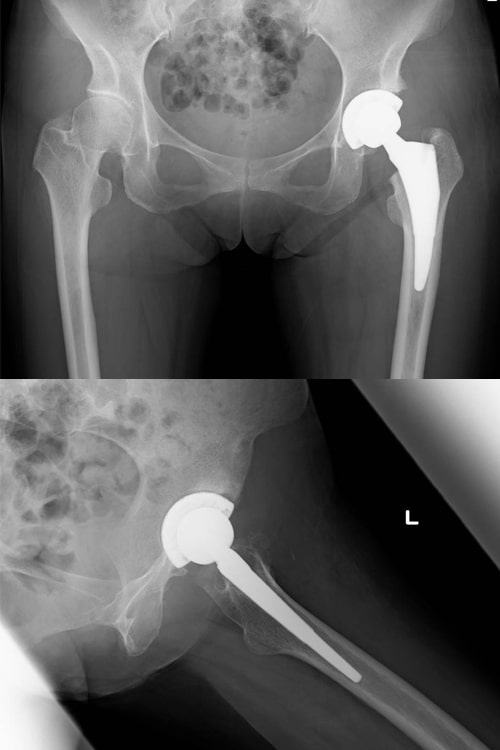

変形性股関節症

主な症状は、股関節の痛みと機能障害です。股関節は鼠径部(脚の付け根)にあるので、最初は立ち上がりや歩き始めに脚の付け根に痛みを感じます。関節症が進行すると、その痛みが強くなり、場合によっては持続痛(常に痛む)や夜間痛(夜寝ていても痛む)に悩まされることになります。一方日常生活では、足の爪切りがやりにくくなったり、靴下が履きにくくなったり、和式トイレ使用や正座が困難になります。また長い時間立ったり歩いたりすることがつらくなりますので、台所仕事などの主婦労働に支障を来たします。階段や車・バスの乗り降りも手すりが必要になります。

患者さんの多くは女性ですが、その場合原因は発育性股関節形成不全の後遺症や股関節の形成不全といった子供の時の病気や発育障害の後遺症が主なもので、股関節症全体の80%といわれています。最近は高齢社会となったため、特に明らかな原因となる病気に罹ったことが無くても年齢とともに股関節症を発症してくることがあります。

変形性股関節症の治療では、初期にはまず消炎鎮痛剤の内服を行います。またもし過体重があるようでしたらダイエットも考えてください。心理的抵抗がなければ杖の使用もお薦めします。一方、痛みがあるとどうしても歩かなくなり筋肉が衰えてしまいますので、できれば水中歩行や水泳(平泳ぎを除く)を行っていただくと理想的です。運動療法はその他の方法もありますが、運動療法はどうしても疼痛を誘発してしまう可能性がありますので、慎重に始めて徐々に強度を高めていくことがポイントです。これらの保存療法でも症状が取れない場合は手術療法を考えます。初期のうちでしたら自分の骨を生かして行う骨切り術の適応ですし、関節の変形がすすんでいる場合は人工股関節手術の適応となります。